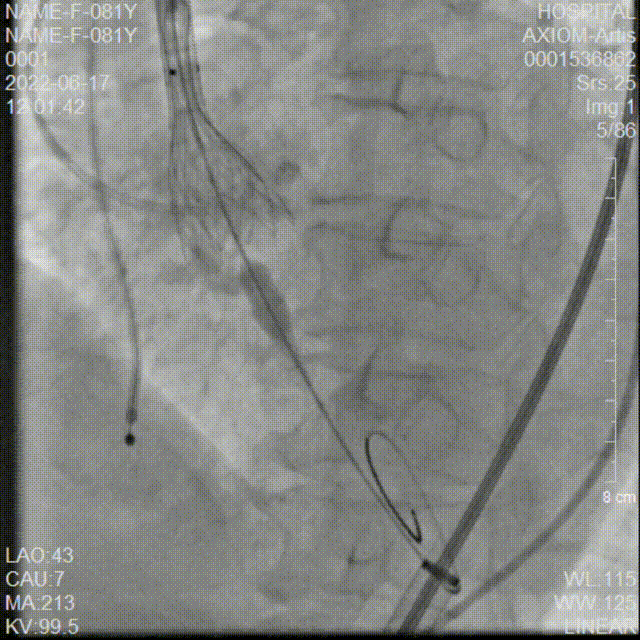

20mm球囊预扩